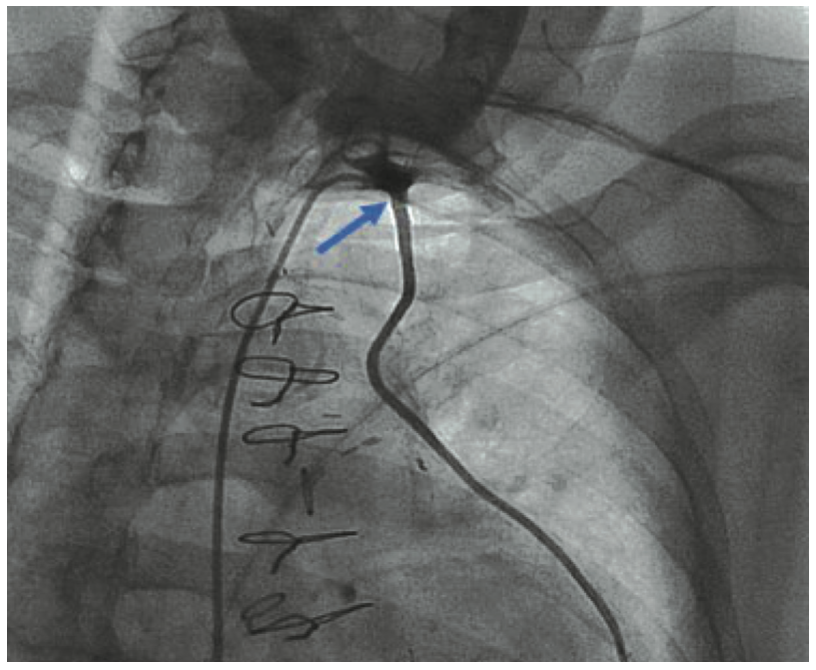

A diagnostic right heart catheterization revealed high Fick cardiac output/cardiac index, severe pulmonary hypertension (70/27, [40 mmHg]), moderate to severely elevated left-sided filling pressures (left ventricular end-diastolic pressure [LVEDP] 28 mmHg), pulmonary capillary wedge pressure (24 with V-waves to 40 mmHg), and moderately elevated right-sided filling pressures. A diagnostic left heart catheterization revealed severe, multivessel native CAD. Bypass graft anatomy revealed severe graft disease in the ostial LIMA to LAD (80% stenosis with moderate-severe calcification; Figure 1A, Video 1) and mid-distal SVG to OM2-OM3 (mid 80%, distal 99% diffuse stenosis, thrombus, diffuse calcification; Figure 2).

Video 1. Coronary angiogram showing severe stenosis with eccentric, focal calcification at the LIMA ostium.

There was also mild to moderate non-obstructive disease of the SVG to the right PDA. The ostial LIMA lesion was validated with the administration of intracoronary nitroglycerin and later with intravascular ultrasound (IVUS) (Figure 1B), as well as by the observation of severe balloon compression during the interventional procedure, as described below.

As previously described, arterialization of a venous graft6 with calcium deposition in the vessel wall rather than a plaque may be a case where IVL is preferable over atherectomy. Our case represented an arterial conduit with severe calcification in the vessel wall mixed with soft plaque within the vessel (Figure 1B), in a location where rotational and orbital atherectomy would be ill-advised and potentially compromise the safety of the patient. Intravascular lithotripsy provided effective and safe yielding of the lesion in a LIMA segment with ultimate, optimal DES deployment and expansion.